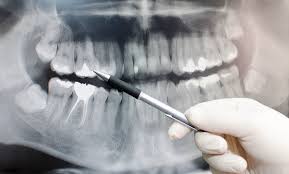

WHAT IS OPG IN DENTAL :-

OPG or Orthopentomogram is special x-ray of the lower face, teeth and jaw. An OPG is a panaromic view of x-ray of the lower face and jaw which displays allthe teeth of upper and lower jaw on a single film.